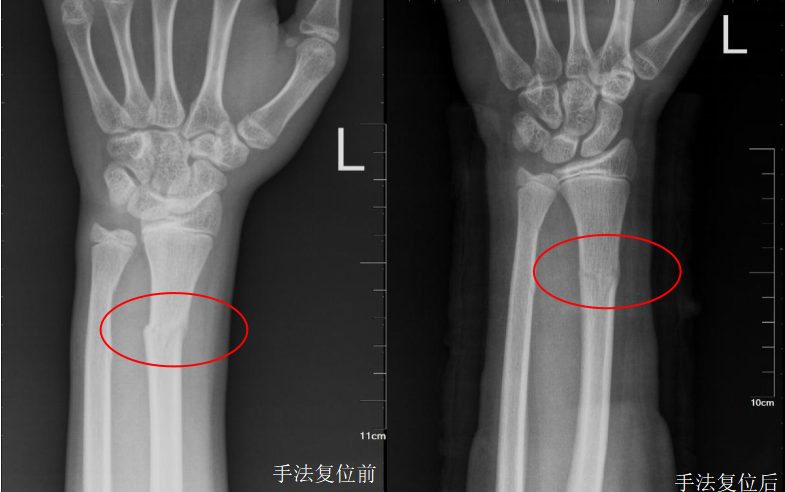

X线检查是骨折首选的影像学检查手段,可以达到快速初步判断的目的

X线检查具有成像速度快、费用低、辐射少的优点,对于有移位的骨折、骨质破坏、关节骨病、不透光异物存留等疾病有很好的诊断价值,因此X线检查成为骨折的首选检查方法。

明显的骨折通过X线片就可以明确诊断,达到辅助临床医生诊断及治疗的目的,复位后只需要遵医嘱并定期复查即可。